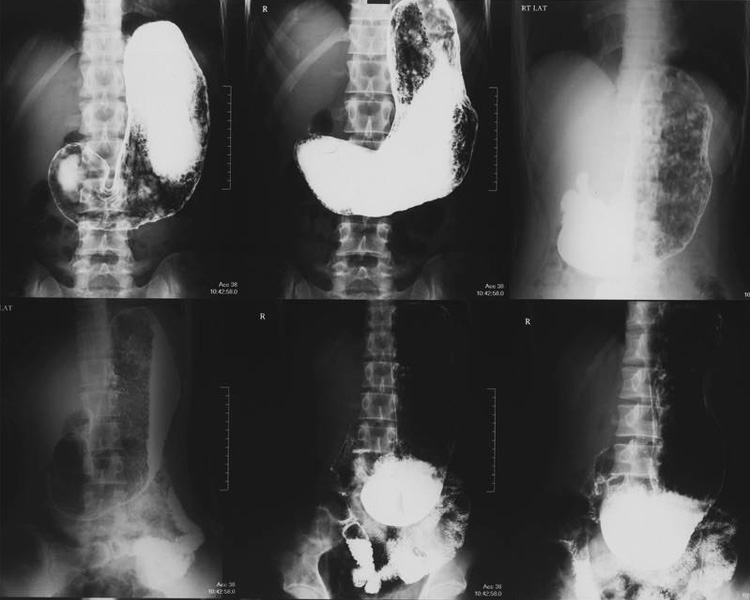

К довольно распространенным нарушениям, связанным с аномальным расположением органов брюшины является спланхноптоз, характеризующийся смещением петель кишки в область малого таза. Заболевание создает ряд проблем с правильным функционированием самого органа, а иногда и соседних, вызывает ухудшение самочувствия пациента. Основываясь на многолетних наблюдениях, можно сделать вывод, что наиболее частым диагнозом является:

- колоноптоз – смещение вниз ободочного сегмента толстой кишки;

- трансверзоптоз – пролапс поперечно-ободочной кишки в виде буквы V.